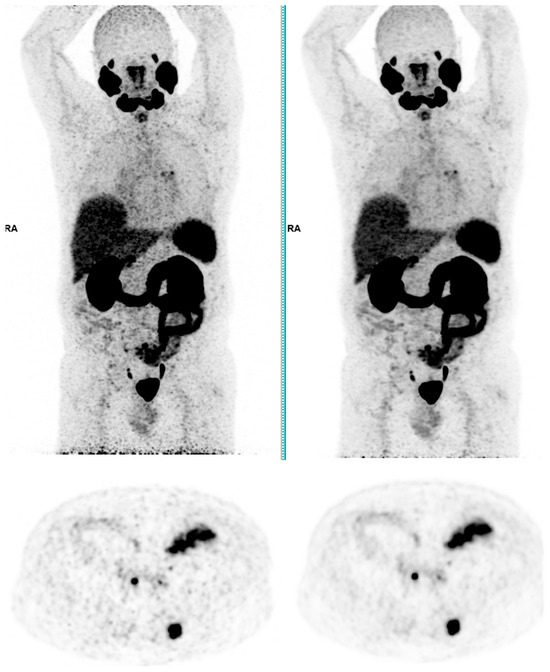

Across the three radiotracers, the AI-denoised images demonstrated a significantly improved performance in the visual analysis compared to conventional PET images. AI-denoised images were rated as interpretable (scores of 3–5) in all cases, compared to 65% for conventional images. Furthermore, an excellent image quality (score of 5) was achieved in 85% of all AI-denoised images, a significant improvement compared to the 50% in standard acquisitions. SubtlePET™ processing resulted in consistently lower noise levels, particularly for 18F-FDG scans, where 85% of images scored 4 or 5 for noise reduction compared to 60% in conventional scans. Lesion detectability was maintained or enhanced across all radiotracers, ensuring no compromise in the diagnostic accuracy. For 18F-FDOPA, a tracer with inherently lower signal-to-noise ratios, the AI algorithm improved the detection confidence by 25% compared to standard protocols. The visual comparison is illustrated through different MIP images and transaxial images (Figure 1, Figure 2, Figure 3 and Figure 4)

For 68Ga-PSMA-11

In the 68Ga-PSMA-11 subgroup, the application of SubtlePET™ also yielded notable quantitative improvements. The SNR rose from a baseline of 9.7 to 15.4 in AI-denoised images, while the CNR improved from 4.6 to 7.5. These gains were especially apparent in areas of moderate tracer uptake, such as pelvic lymph nodes, where subtle lesions became more readily discernible. This enhancement was consistent across BMI groups, indicating robust noise suppression and preserved diagnostic detail even at reduced acquisition times.

Figure 3. Total body 68Ga-PSMA-11 PET CT, MIP and transaxial images (left: without AI denoising; right: with AI denoising).